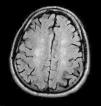

El síndrome de embolismo graso (SEG) es una entidad poco frecuente que ocurre habitualmente entre las 12-72 horas tras fracturas traumáticas de huesos largos de las extremidades inferiores. Se caracteriza por manifestaciones pulmonares, cerebrales y cutáneas. Las anomalías neurológicas son frecuentes (hasta un 86 %) y variables, aunque los pacientes suelen recuperarse sin secuelas. No existen criterios universales para el diagnóstico del SEG, aunque en el caso de sospecha de afectación neurológica se recomienda realizar una resonancia magnética cerebral. Se presenta un caso de SEG con afectación neurológica con demencia como secuela. Esta secuela, relacionada con este síndrome, no se ha encontrado descrita en otras publicaciones.

Fat embolism syndrome (FES) is a rare disease that occurs between 12-72 hours after traumatic long bone fractures. Their main characteristics are pulmonary, cerebral and skin manifestations. Neurological abnormalities are frequent (up to 86 %) and variable, however most of the patients recover without sequelae. There are no universal criteria for fat embolism syndrome diagnosis, but when neurological involvement is suspected an MRI of the head should be performed. We present the case of a patient with FES with neurological involvement who presented dementia as sequela. This sequela, related to FES, has not been found in other publications.